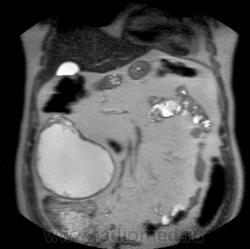

Кистозно-солидное образование н/3 правой почки, солидный компонент хоть и минимальный, но он есть, следует с ним внимательнее разобраться, я бы отнес данное кистозное образование к IV категории по Босняку.

А. эта опухоль больше похожа на "добро" или "зло"?

Добрый вечер. Босняк 4 означает что образование надо рассматривать как злокачественное, пока не будет доказано обратное или подтверждена злокачественная природа.

Сто процентный рак. Без всяких босняков.

Я бы в диф ряде рассмотрел бы эхинококкоз - в нижнем полюсе образования есть перегородка.

А вот метастазов рака почки, по видимому, не видит никто) а они есть)

Пока нет данных морфологии по этой кисте - не отказываюсь от своего мнения об эхинококке. Статьи по изолированому эхинококку почек(всего 3 процента по статистике) и других редких локализаций можно посмотреть здесь http://ifolder.ru/21262829, если кому-то еще интересна дискуссия